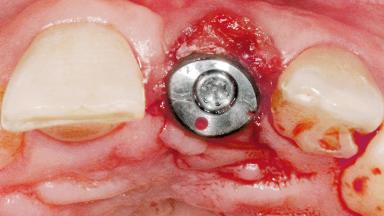

Late Flapless Placement of an Implant in a Maxillary Left Central Incisor Site

Type of Implants One-Piece

Attachment One-Piece

Abutment Type Standard